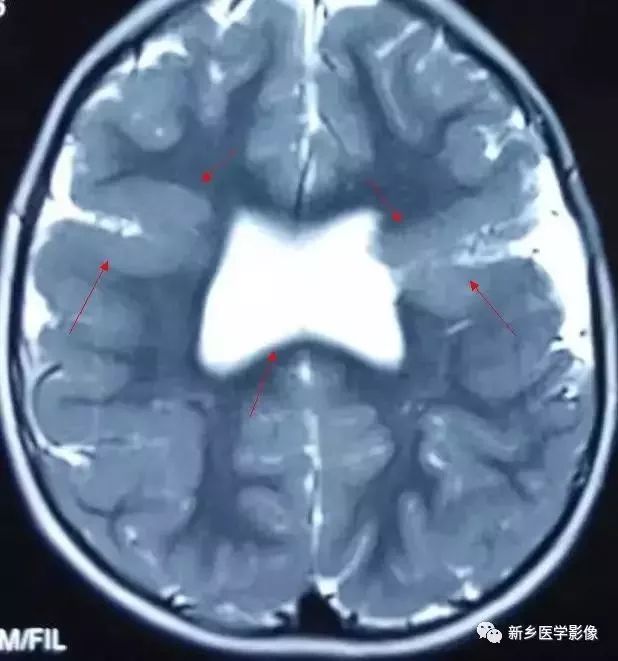

❹ 一侧室间孔阻塞

脑脊液主要产生于脑室的脉络膜丛。当一侧室间孔阻塞时,同侧侧脑室脉络膜丛产生的脑脊液不能进入三脑室,脑脊液在侧脑室内聚积,CT和MR检查表现为一侧侧脑室扩大,扩大明显时可有中线结构向对侧移位,主要原因有室间孔附近的肿瘤、囊肿、囊虫及炎性粘连。

确定一侧侧脑室扩大为室间孔阻塞所致的要点包括:

- 一侧侧脑室扩张明显,有张力;

- 透明隔向对侧移位;

- 扩一大的侧脑室周围没有能够导致该侧侧脑室扩大的其他可以解释的原因。